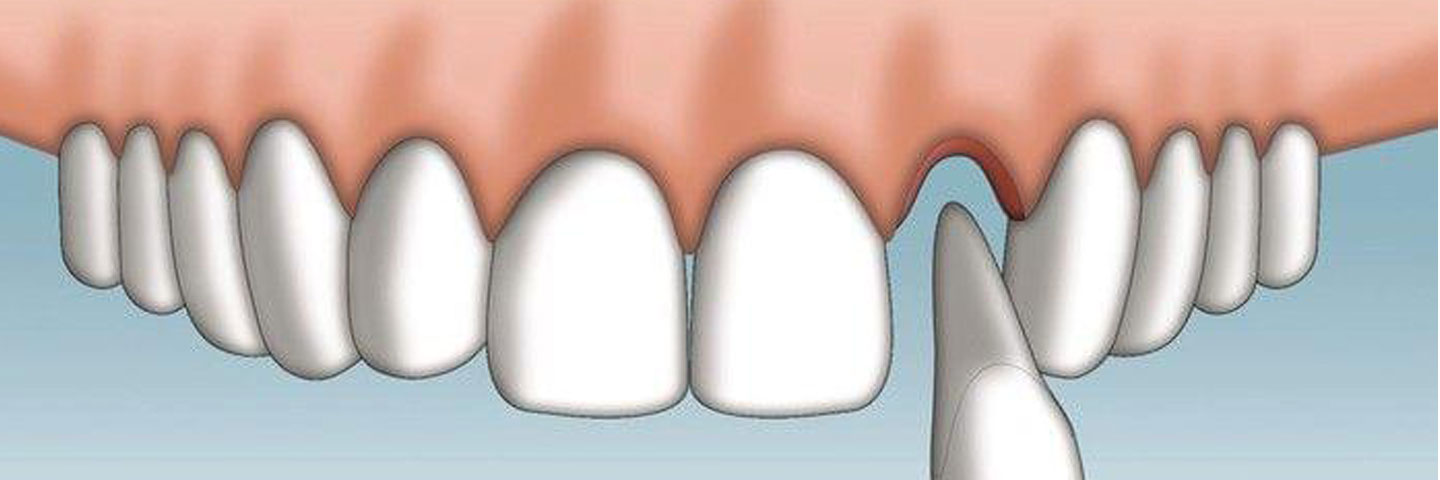

Реплантация зуба: Этапы и особенности операции